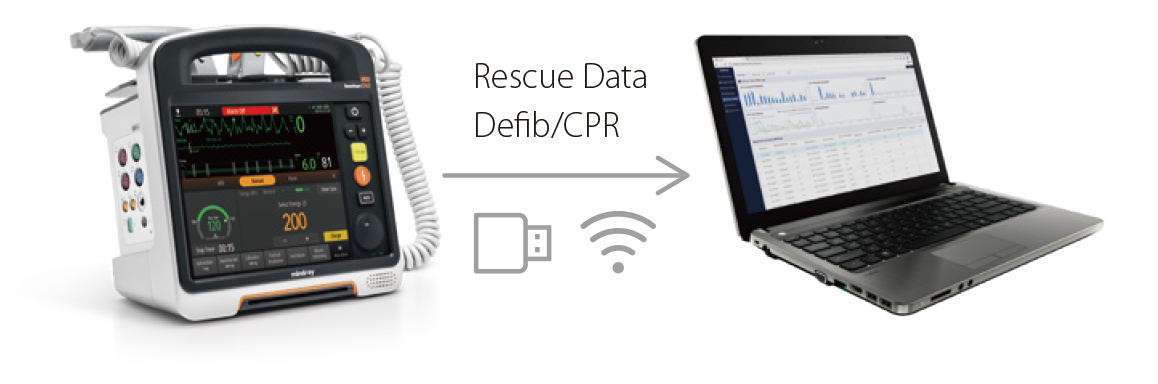

Kurtarma ??geni, Daha Kapsaml?

- D60â?n yap?land?r?lm?? bilgilendirme protokolleri, sonraki resÞsitasyon olaylar?nda resÞsitasyon ekiplerinin performans?n? art?r?r.

- D60'daki e?itim modu, ger?ek operasyon deneyimi elde etmenize yard?mc? olur.

Daha H?zl? ResÞsitasyon

Yap?land?r?lm?? Bilgilendirme

- D60â?n yap?land?r?lm?? bilgilendirme protokolleri, sonraki resÞsitasyon olaylar?nda resÞsitasyon ekiplerinin performans?n? art?r?r.

Uygulamal? E?itim

- D60'daki e?itim modu, ger?ek operasyon deneyimi elde etmenize yard?mc? olur.